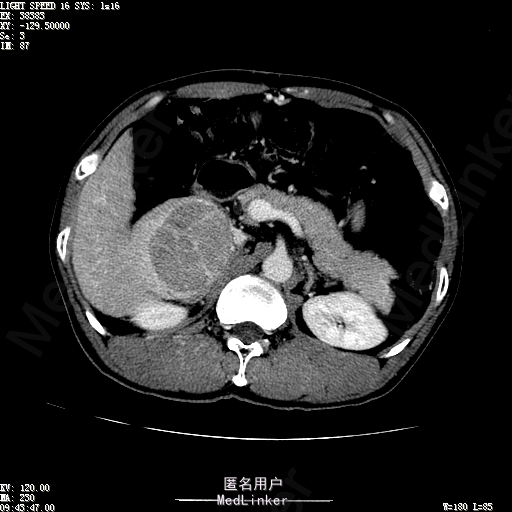

查体:体温36.4℃,脉搏76次/分,呼吸18次/分,血压110/70mmHg。神志清晰,发育正常,营养中等,体位自如,表情安静,慢性病容,检查合作。皮肤粘膜颜色正常,无瘀点、紫癜,有肝掌,无蜘蛛痣,无水肿,毛发的生长与分布正常。浅表淋巴结浅表淋巴结未触及肿大。无巩膜黄染,结膜正常。口唇红润,粘膜正常,舌正常,牙龈正常,扁桃体无肿大,无咽部充血。颈部外形对称,颈静脉正常,肝颈静脉回流征阴性,气管居中。甲状腺正常,无颈部血管杂音。胸部形态正常,呼吸运动平稳规律,无呼吸困难,肋间隙正常。触诊语颤正常,无胸膜摩擦感,肺下界位于右锁骨中线第六肋间。呼吸音正常,未闻及干湿啰音,无胸膜摩擦音。无心前区隆起,心尖搏动正常,心率:76次/分,心律齐,心音正常,无杂音,无心包摩擦音。无大动脉及周围血管征,无奇脉及交替脉,无水冲脉,无枪击音,腹型对称,无腹壁静脉曲张,未见胃肠型及蠕动波,无瘢痕,脐部正常。无压痛,无反跳痛,无腹肌紧张,无腹部包块。肝未触及,Murphy征阴性,脾未触及,肾未触及,无移动性浊音。无肝区叩击痛,无肾区叩击痛,无脾区叩击痛。肠鸣音正常4次/分,无气过水声。外阴及肛门:未查。四肢正常,关节正常,无下肢水肿,无下肢静脉曲张,无杵状指趾。 辅助检查:彩超:肝表面欠光滑,肝内占位5.2*5厘米 ct如下图

诊断:乙肝肝硬化 代偿期 原发性肝癌。 患者病史明确,目前化验转氨酶轻度升高,说明有活动性肝损伤,白蛋白降低提示肝脏合成代谢功能下降,AFP从一年前至今逐渐升高,提示活性肿瘤细胞增多。CT所见明确诊断肝癌,并有周围卫星灶,应近期行TACE治疗。 处置:DSA下肝动脉造影及TACE 手术简要经过:患者平卧位,术区皮肤消毒,铺手术巾,2%利多卡因局麻后,Seldinger法穿刺右股动脉,入血管鞘,5F猪尾管腹主动脉造影,超滑导丝yidao5F RH管腹腔干、肠系膜上动脉、左肾动脉分别造影,腹腔干造影时,见肝右叶7-8处小结节样肿瘤染色,未见外凸生长较大病灶染色。微导管超选肝右动脉注入三氧化二砷碘油混悬液10毫升,横结肠遮挡部位见较大病灶有伞状碘油沉积。复查造影未在见肿瘤染色,拔出导管和血管鞘,穿刺处压迫止血,加压包扎。术毕。

患者术后8天来,无不适,无发热,无腹痛和腹胀,无恶心呕吐,食欲睡眠好,尿便正常。 查体:神志清,巩膜无黄染,心肺听诊无异常,腹软,无压痛,肝脾肋下未触及,移动性浊音阴性,双下肢无浮肿。 复查化验结果:丙氨酸氨基转移酶 116 U/L、天门冬氨酸氨基转移酶 41 U/L、胆碱酯酶 1995 U/L↓、总蛋白 56.3 g/L、白蛋白 25.9 g/L。白细胞计数 5.8 10^9/L、红细胞计数 3.18 10^12/L、血小板计数 175.0 10^9/L、*血红蛋白 83 g/L、血小板分布宽度 15.7 、血小板压积 0.175 %、*红细胞压积 24.6 %、平均红细胞血红蛋白 26.1 pg、平均红细胞血红蛋白浓度 337.0 g/L、平均红细胞体积 77.5 fL、平均血小板体积 10.0 fL、嗜碱性粒细胞百分比 0.4 %、嗜碱性粒细胞数量 0.02 10^9/L、中性粒细胞百分比 70.4 %、中性粒细胞数量 4.10 10^9/L、嗜酸性粒细百分比 2.1 %、嗜酸性粒细胞数量 0.12 10^9/L、单核细胞百分比 12.2 %、单核细胞计数 0.7 10^9/L、淋巴细胞数量百分比 14.9 %、淋巴细胞计数 0.9 10^9/L。甲胎蛋白 23564.00 ng/mL 患者术后第8天开始行FOLFOX6化疗。CT上可见明显碘油沉积,术后甲胎蛋白下降治疗有效。嘱患者术后必须定期复查